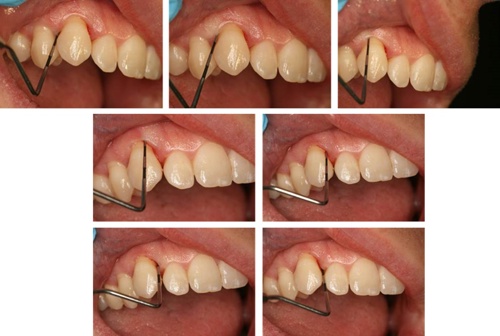

The probe should be inserted parallel to the root surface into the periodontal pocket and ‘walked’ around the gingival margin (see figure: Walking the probe). Probing depth should be measured at six sites per tooth.

A PCP 12 probe is ‘walked’ around the gingival margin of the tooth.